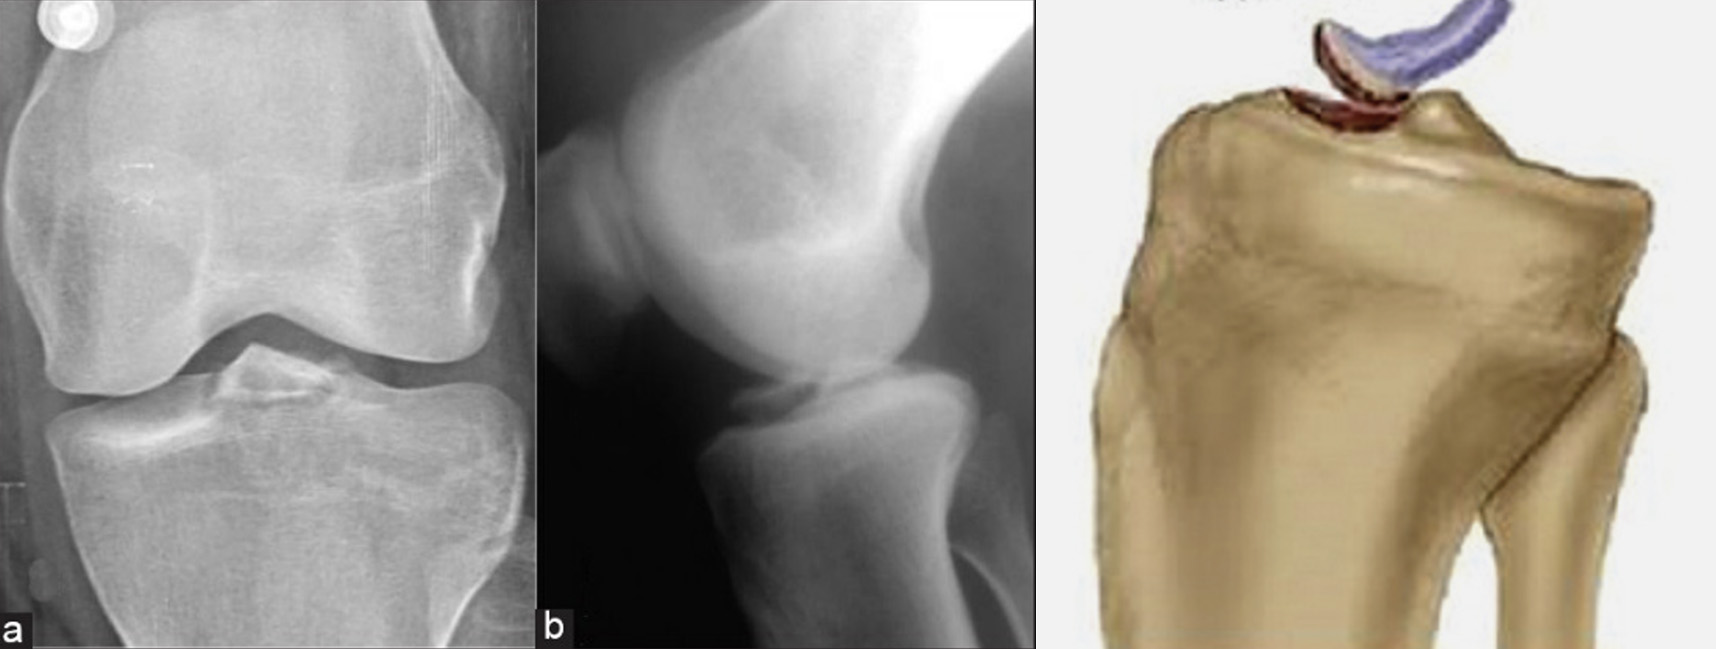

Nos casos em que estejamos perante um arrancamento ósseo da inserção distal do LCA, poderá igualmente ser visível no Raio X – Figura 6.

Avulsão óssea da inserção distal do LCA, imagem de Rx e representação gráfica

Figura 6 – Avulsão óssea da inserção distal do LCA, imagem de Rx e representação gráfica